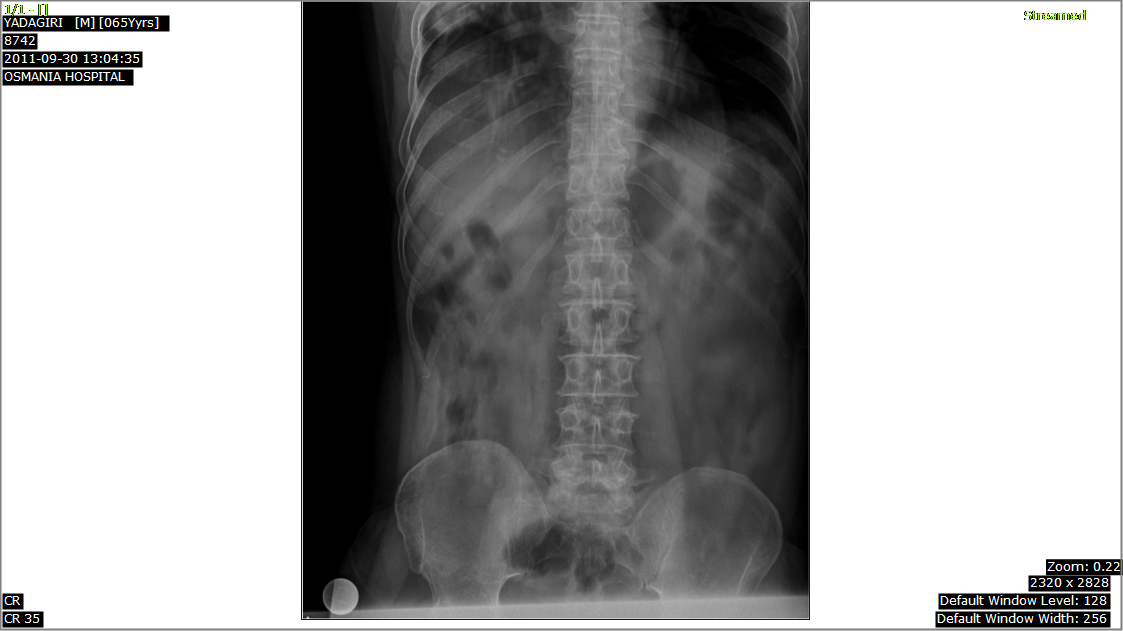

Plain Xray of Pelvis with both hips shows the dense sclerotic and deformed head of Rt femur with changes in acetabulum left hip is apparently normal on X ray